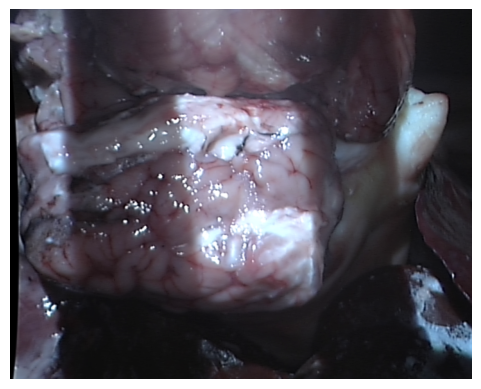

(a) The capture of a sheep’s liver using the dVRK laparoscope.

Refer to caption

(b) An example image captured which contains multiple ex vivo tissue.

Figure 2: Shown in (a) and (b) is the setup for the medical dataset collection. Image (a) shows an example of tissue captured using the dVRK laparascope. (b) does not contain projection patterns and would be fed as an input to the neural network.

Medical dataset: A medical dataset was created using the da Vinci Research Kit (dVRK) (Kazanzides et al. 2014) to extend the evaluation of the model onto real images. The dVRK was chosen as it is the research model of the surgical system that is used in clinical practice and commonly used for research in this field. A structured light projector was attached to a da Vinci camera arm and the stereo laparoscope of the machine was used to capture scenes with projected patterns on medical phantoms and ex-vivo organs from sheep, cows and chicken. Gray code was used for this dataset with 9 patterns. The decoding was performed using the three phase algorithm (Xu et al. 2022). A turning table was used to hold the objects and were rotated for multiple perspectives. Fig. 2 shows the setup and an example image which would be fed as the input to the neural network (an image without projection patterns).